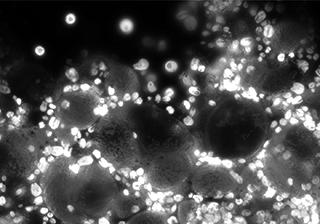

微弱生物熒光

牛肺動脈內皮細胞 - MIchrome CMOS 相機

牛肺泡上皮細胞熒光成像-TrueChrome HDMI 相機